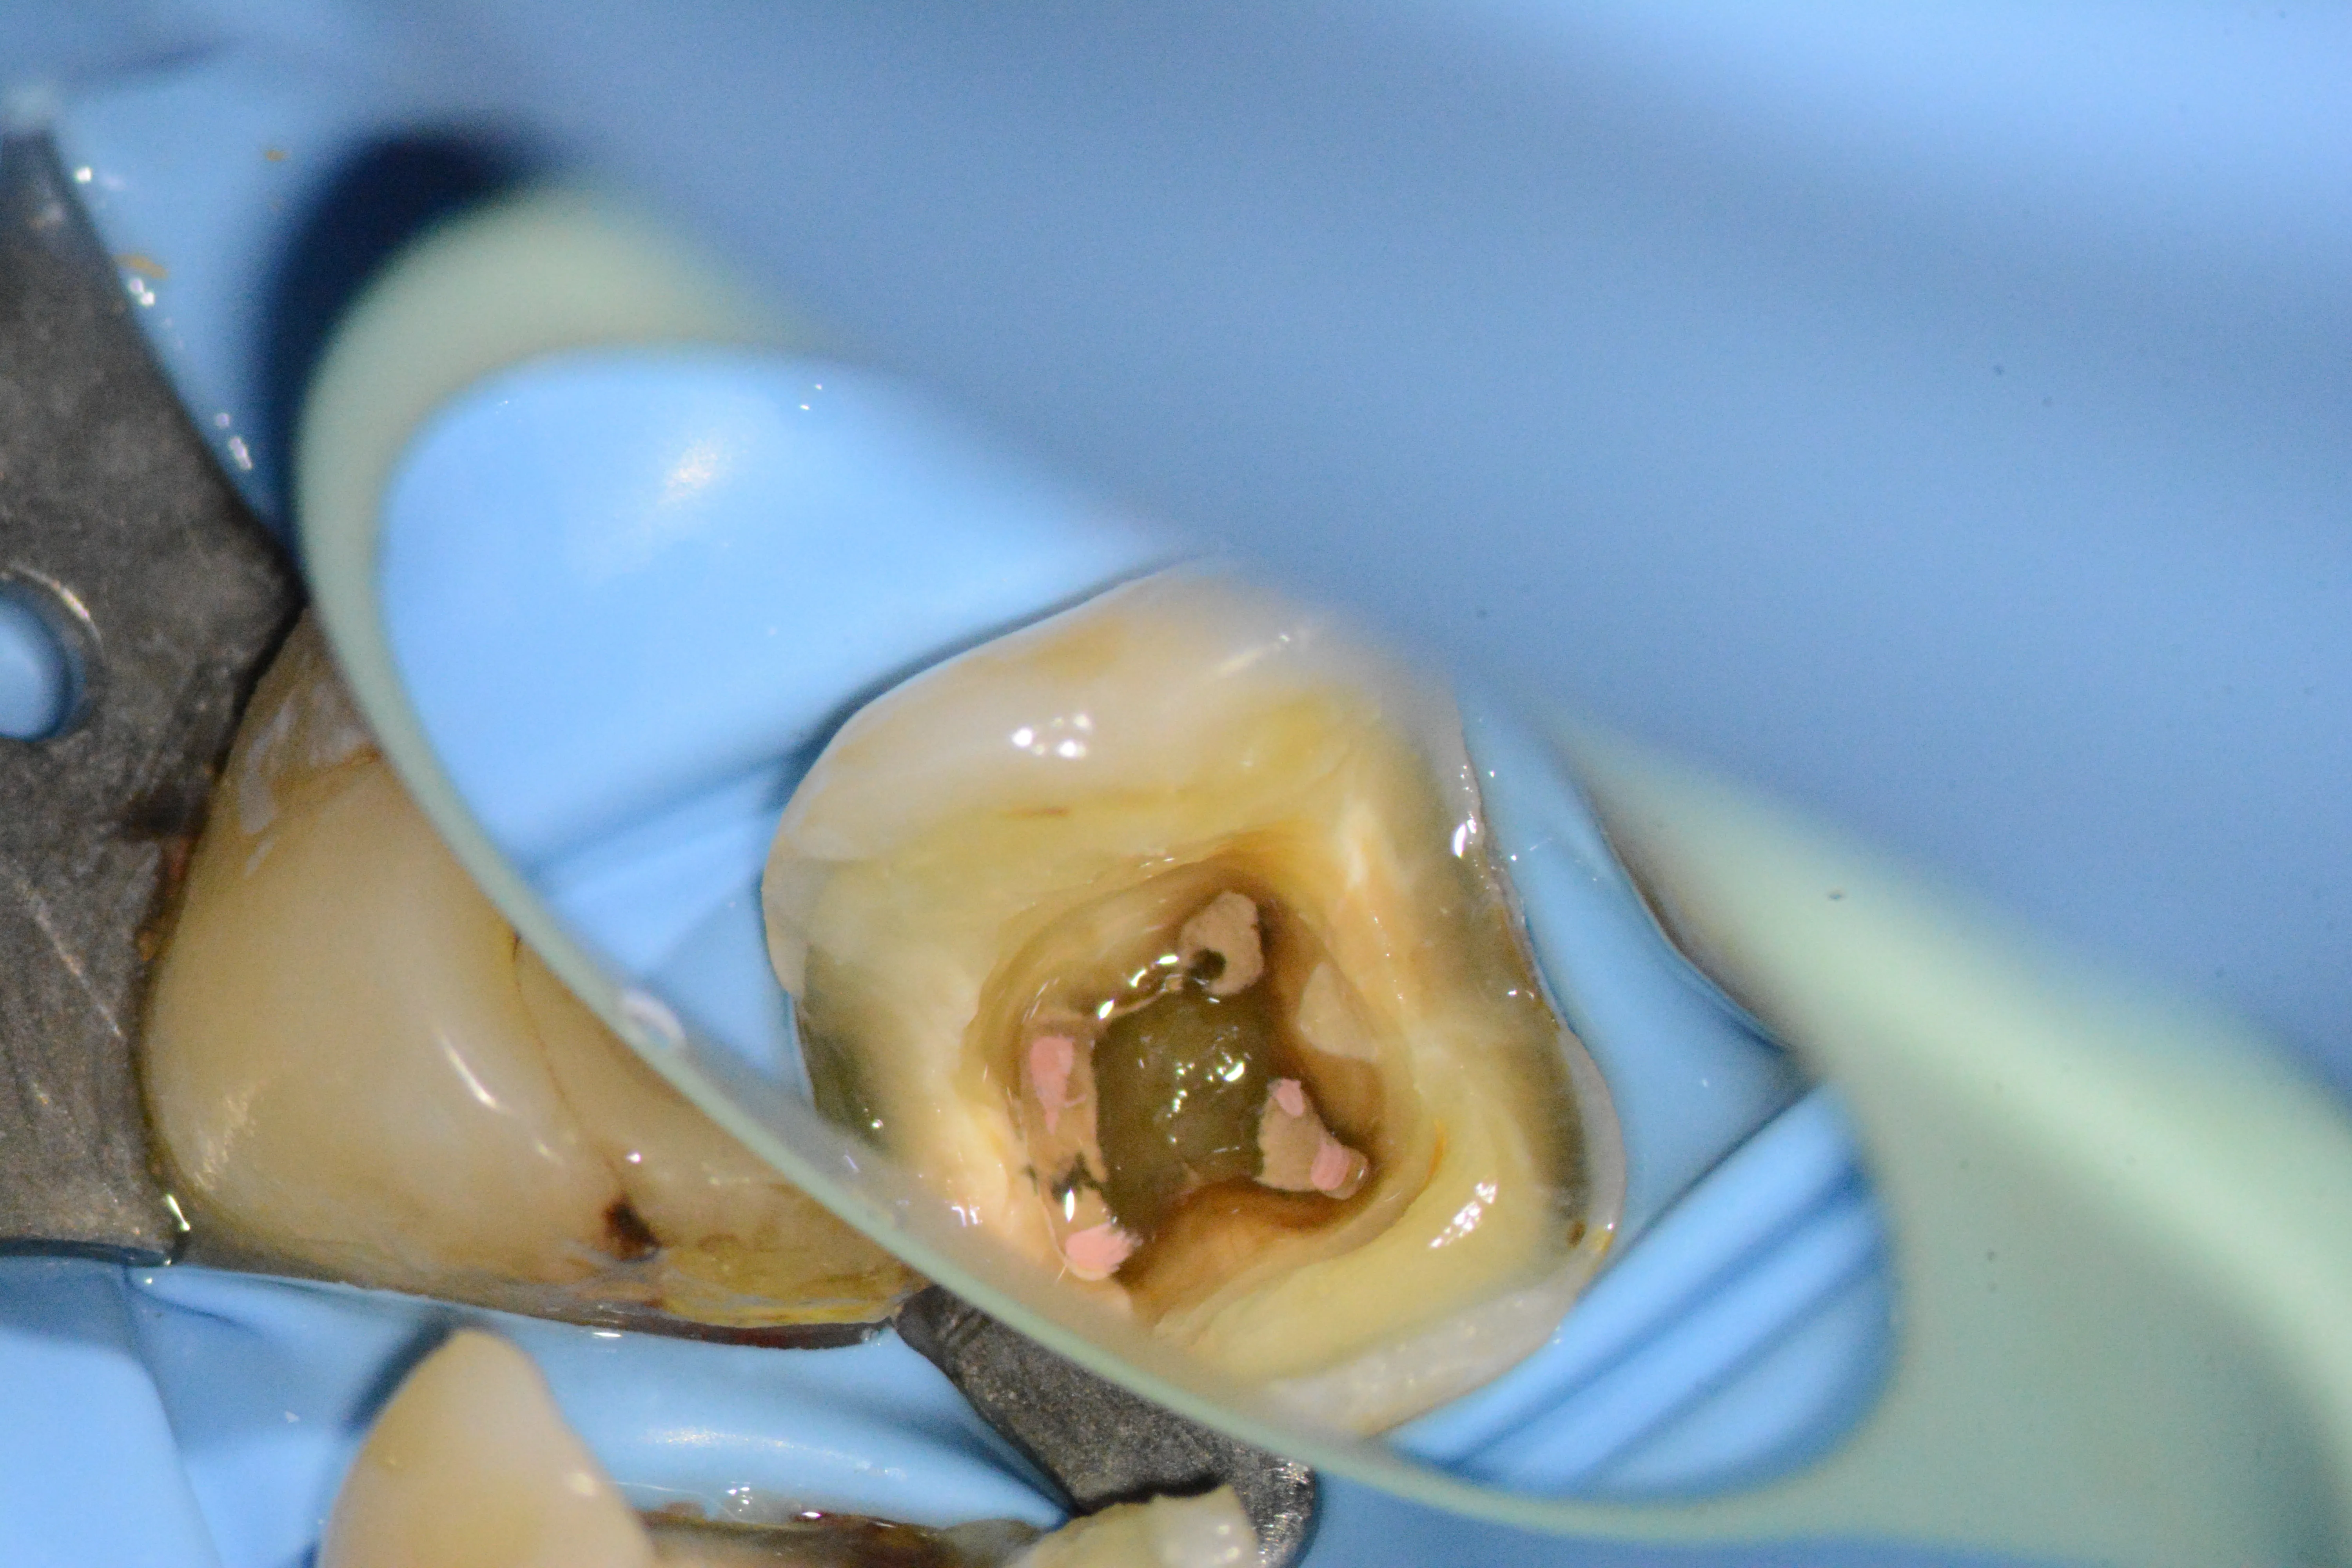

10 – Aspectul instrumentului fracturat mobilizat